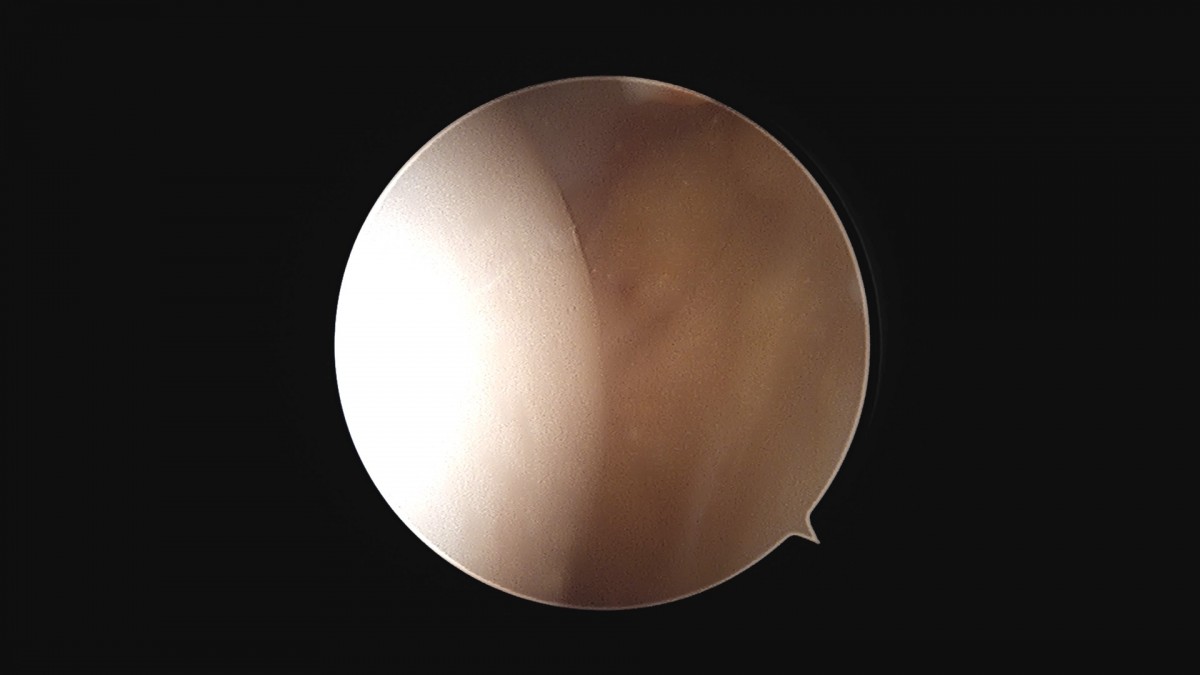

이재상원장님 발목 활액막 절제술 및 인대 봉합술 신진O 환자

dae765e4d9ac96aee867c9d6292d8784_1758003731_8482.jpg